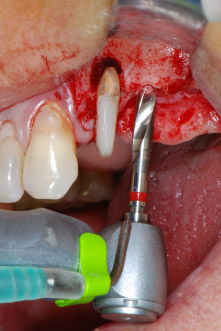

имплантологичен мотор

Фиг. 8: Препарация на имплантологичното ложе близо до пода на максиларния синус в позиция 25, изпълнена с новия имплантологичен мотор.

Имплантологичното ложе е подготвено в позиции 25 и 26 с ротиращи инструменти, използвайки обратен наконечник 20:1 с усъвършенстван и мощен имплантологичен мотор (Implantmed, W&H) (Фиг. 8).

Следващата препарация близо до синуса отново е извършена с пиезохирургичен накрайник (Piezomed, накрайник S2).